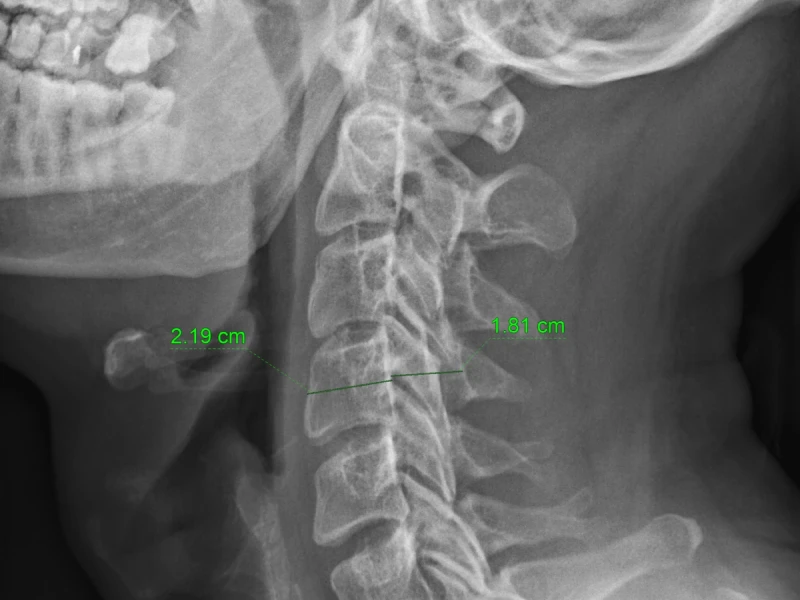

Guia para interpretar una radiografía de columna cervical

En trauma, la Rx cervical debe leerse con método y con humildad diagnóstica. La sistemática ABCD te ayuda a no omitir pasos: alineación, hueso, discos/articulaciones y partes blandas. La primera pregunta siempre es si el estudio es adecuado (cobertura C1–T1). Si hay signos de inestabilidad, déficit neurológico o sospecha clínica alta, la decisión se apoya en TC y RM según el objetivo.